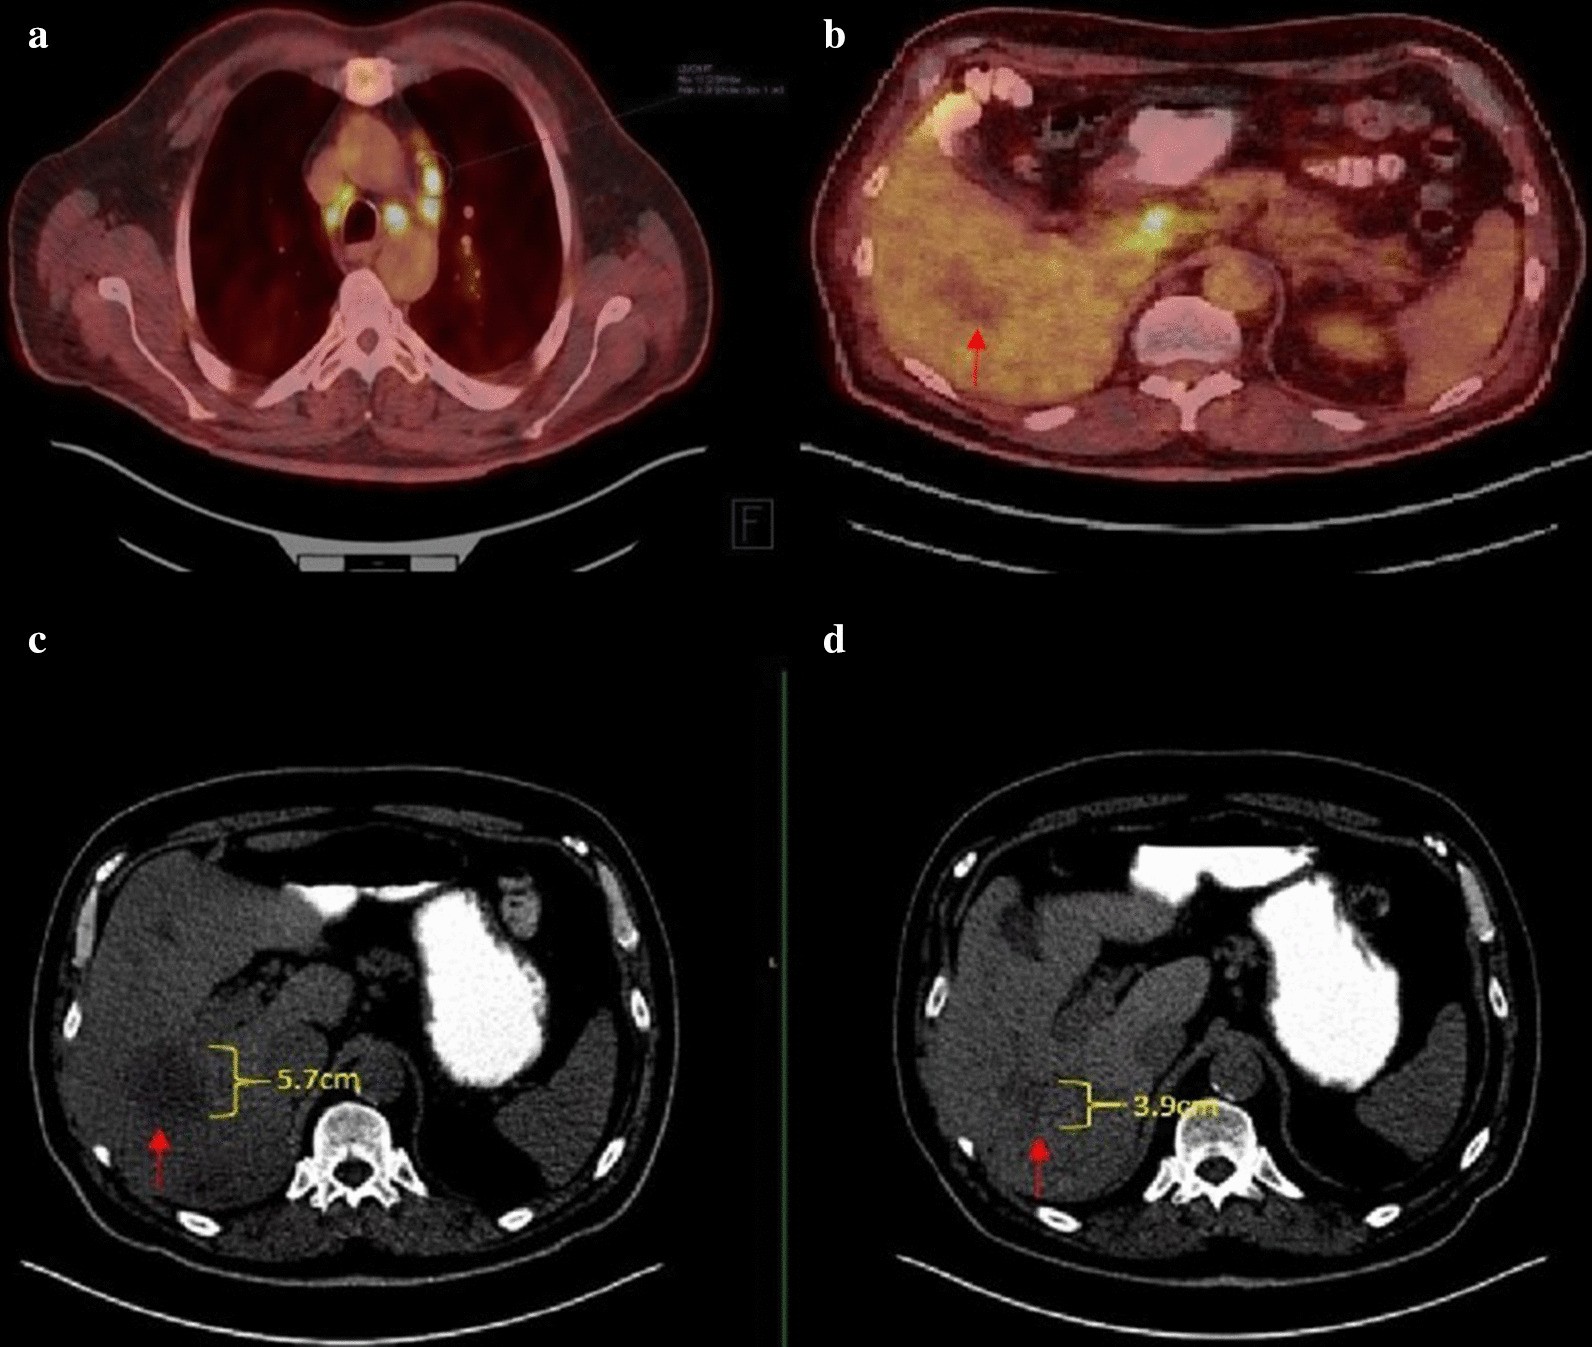

Fig. 1

a FDG-PET/CT demonstrating hypermetabolic mediastinal lymph nodes. b FDG-PET/CT showing a hypermetabolic portacaval lymph node, though the known liver metastasis was not FDG-avid (red arrow). Below these PET images, two CT scans of the abdomen & pelvis are shown: one before treatment was initiated (c) and one 6 months after treatment was completed (d). The dominant right liver lesion decreased from 5.7 × 4.4 cm to 3.9 × 3.6 cm in size (red arrow)